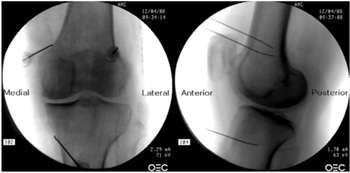

Figura 1

Figura 2

Figura 3

Figura 4